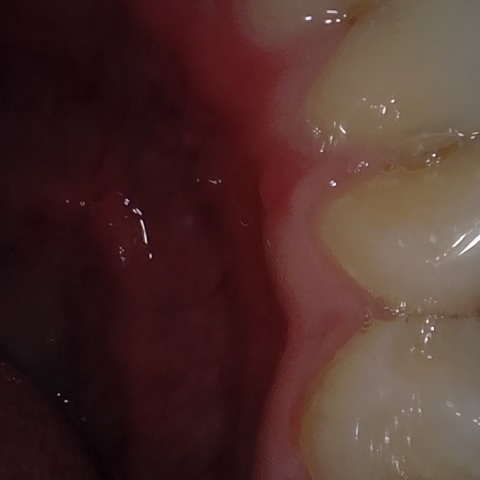

NHD20794

Annotated as "Good"

Original Image Rendering Image